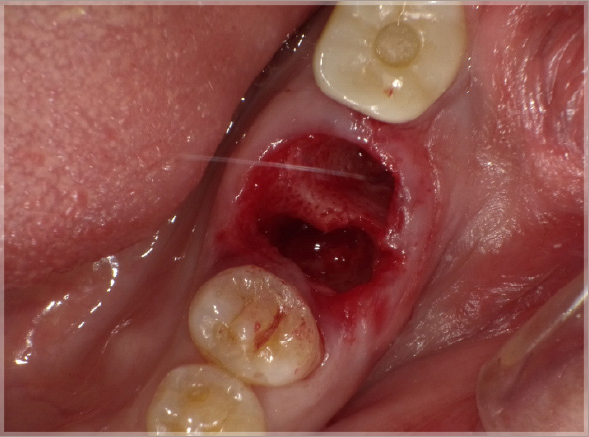

上記の写真はリッジプリザベーションにPRGFを用いたもので、非常に高い効果を得ることができます。

●PRGFを利用した場合

抜歯直後

抜歯してできた穴にPRGFを入れると、上皮や骨の再生が促進され、短期間で抜歯窩がふさがります。また、抜歯後の痛みと腫れも軽減します。

一方、自然治癒を待つ場合には、穴が完全にふさがるまでに数ヶ月かかります。その間にドライソケット(抜歯窩治療不全)になったり、食べ物が詰まるなど、痛みや悪臭を伴うこともあります。